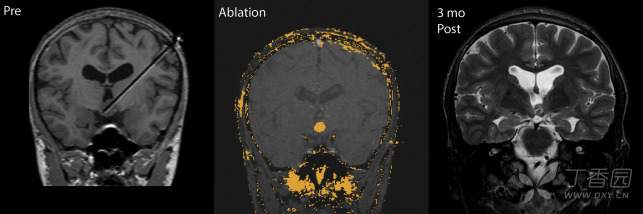

<LITT技术去除癫痫病灶前后效果>

<LITT技术消融脑内胶质瘤前后效果图>